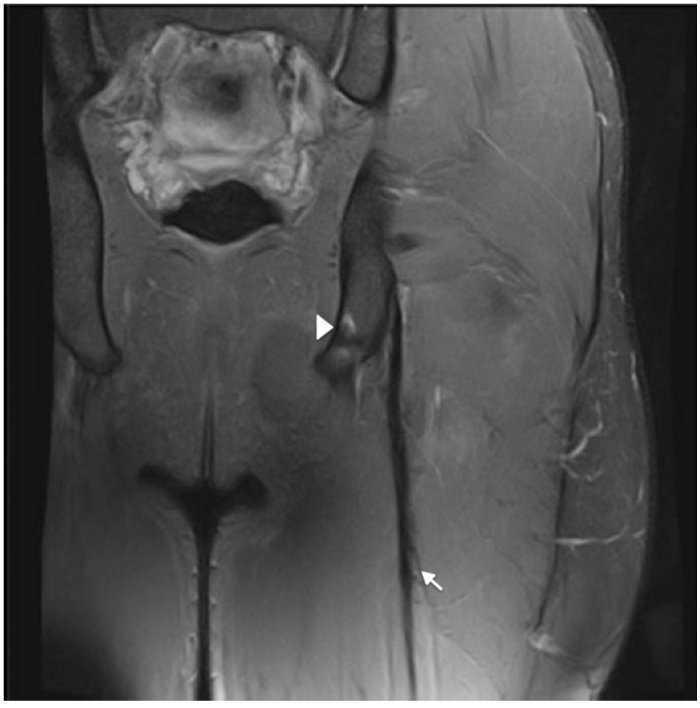

Figura 1 Las imágenes coronal y axial en T2 con saturación grasa del isquiotibial izquierdo muestran rotura parcial de fibras en la UMT proximal de PLBF representadas por un área de alta intensidad de señal adyacente a la UMT (flecha). Se observa también rotura de algunas fibras del semitendinoso (+). Vientre muscular semitendinoso (ST), porción proximal del bíceps femoral largo (long head biceps femoris [LHBF]), tendón semimembranoso (punta de flecha) y nervio ciático (*). En el corte coronal se observa edema muscular de patrón en pluma de ave.